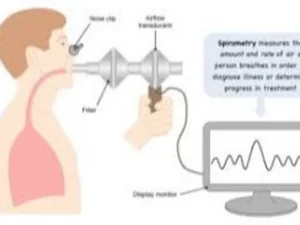

3. Pulmonary Function Tests PFTs

- You will breath forcefully into a machine to determine the volume of air in your lungs

Luanne's provider perscribes a chest X-ray and PFT. The confirm that she is at a moderate Stage 2 disease with forced expiratory volume in one second FEV1 65% of normal. Luanne has many questions, how should the nurse respond?